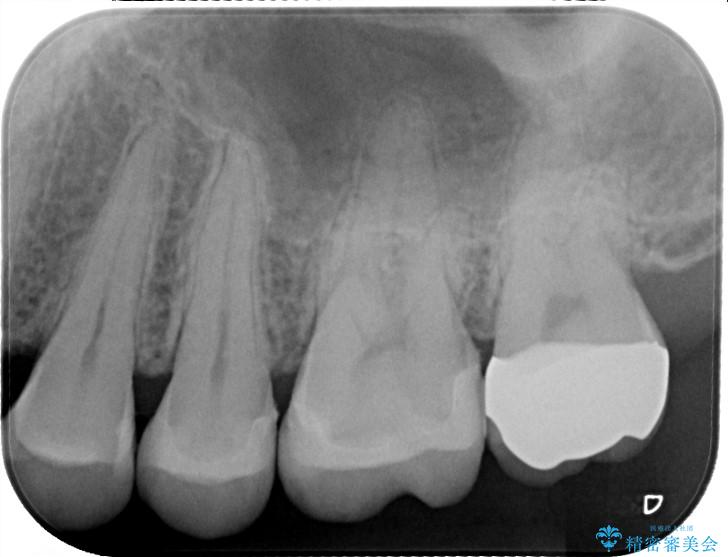

- 銀歯の入っている部分にフロスが引っかかるため、銀歯を適合の良い白いセラミックインレーにやりかえることを提案させていただきました。

一番奥の歯は銀歯に覆われている範囲が多いため、強度などを踏まえ被せ物にしました。

その他2本は詰め物です。